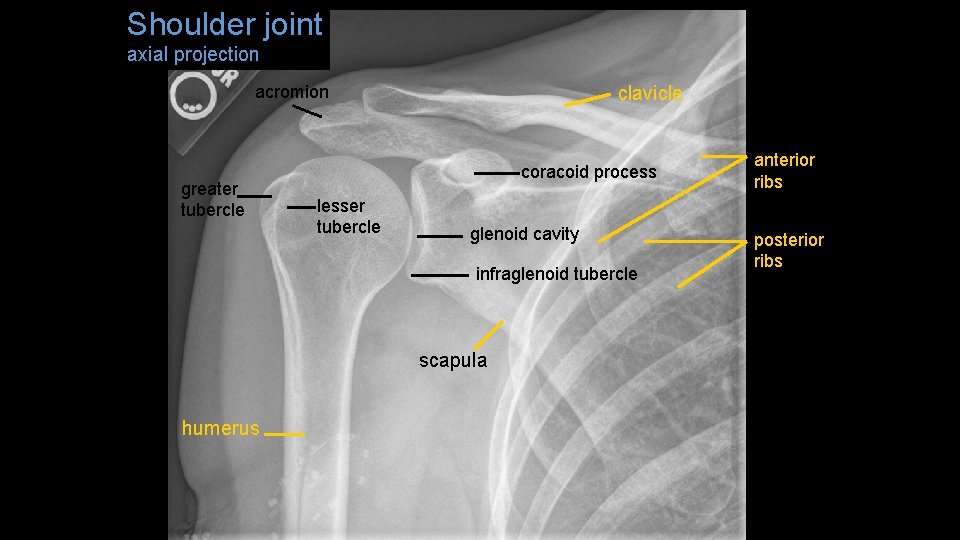

Shoulder joint axial projection acromion greater tubercle clavicle coracoid process lesser tubercle glenoid cavity infraglenoid tubercle scapula humerus anterior ribs posterior ribs